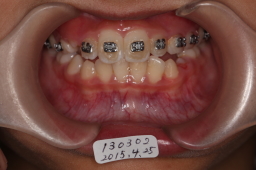

2015年04月25日

上顎犬歯が生えるのを待っています。